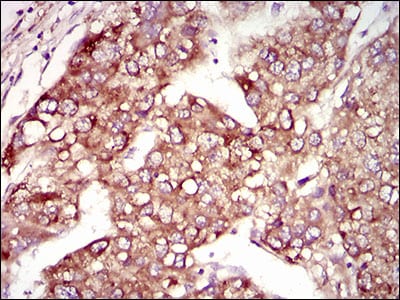

分类: 科研抗体货号: 30470P别名: HIWI2; MIWI2应用: WB,IHC,FCM反应种属: Human

分类: 科研抗体货号: 30470A别名: HIWI2; MIWI2应用: WB,IHC,FCM反应种属: Human